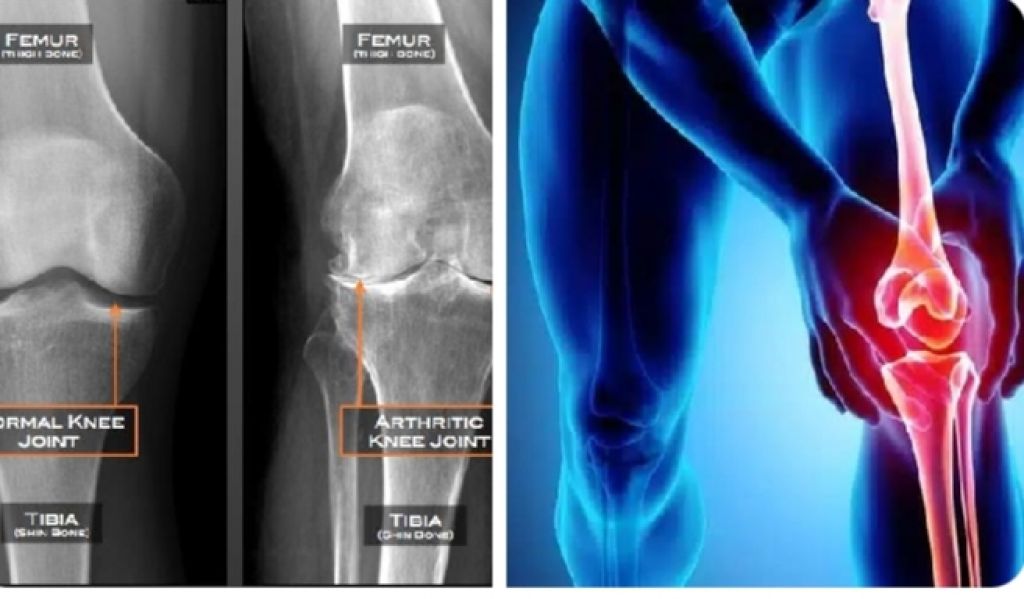

Kerusakan sendi/osteoarthritis/pengapuran ini salah satu penyebab kecacatan. Penderitanya kehilangan kenyamanan untuk berjalan dan beraktivitas karena nyeri yang terus menerus. Dan kasusnya banyak sekali.

Kerusakan sendi tidak secara langsung membuat orang meninggal, tapi sangat mungkin menyebabkan kecacatan.

Nyeri saat berjalan, bahkan berdiri, sampai akhirnya tidak bisa berjalan karena sendi lututnya rusak.